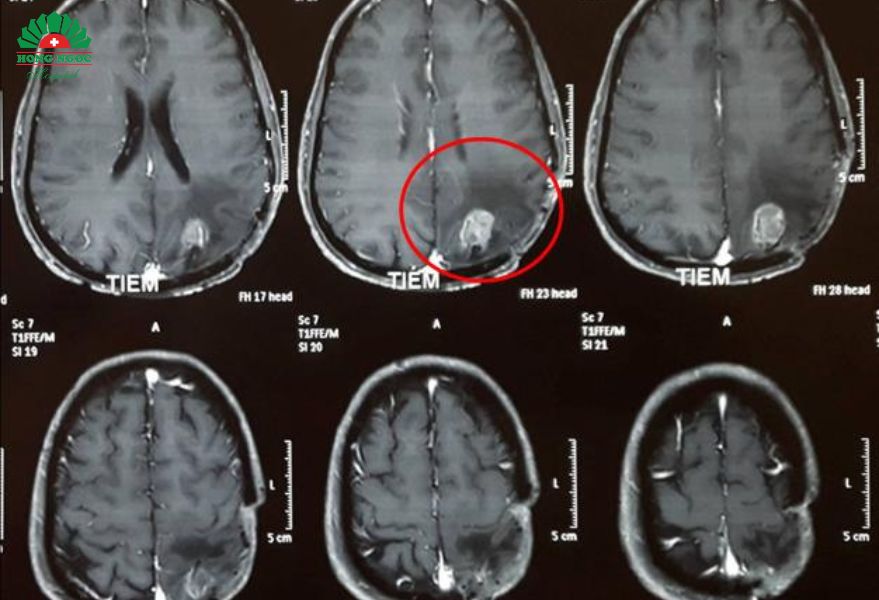

Bệnh nhân bị u màng não được phẫu thuật tại BVĐK Hồng Ngọc